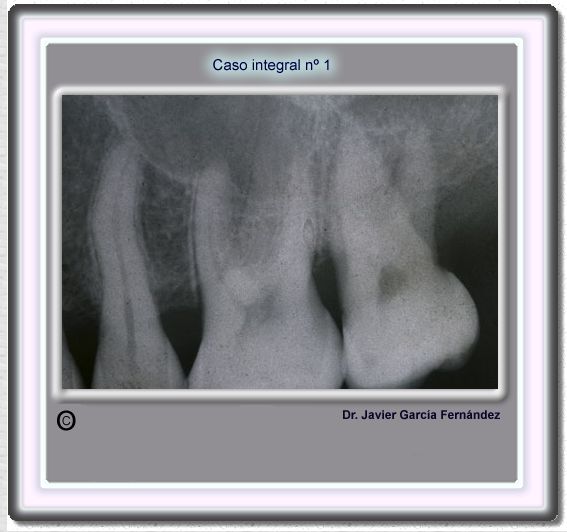

image 18